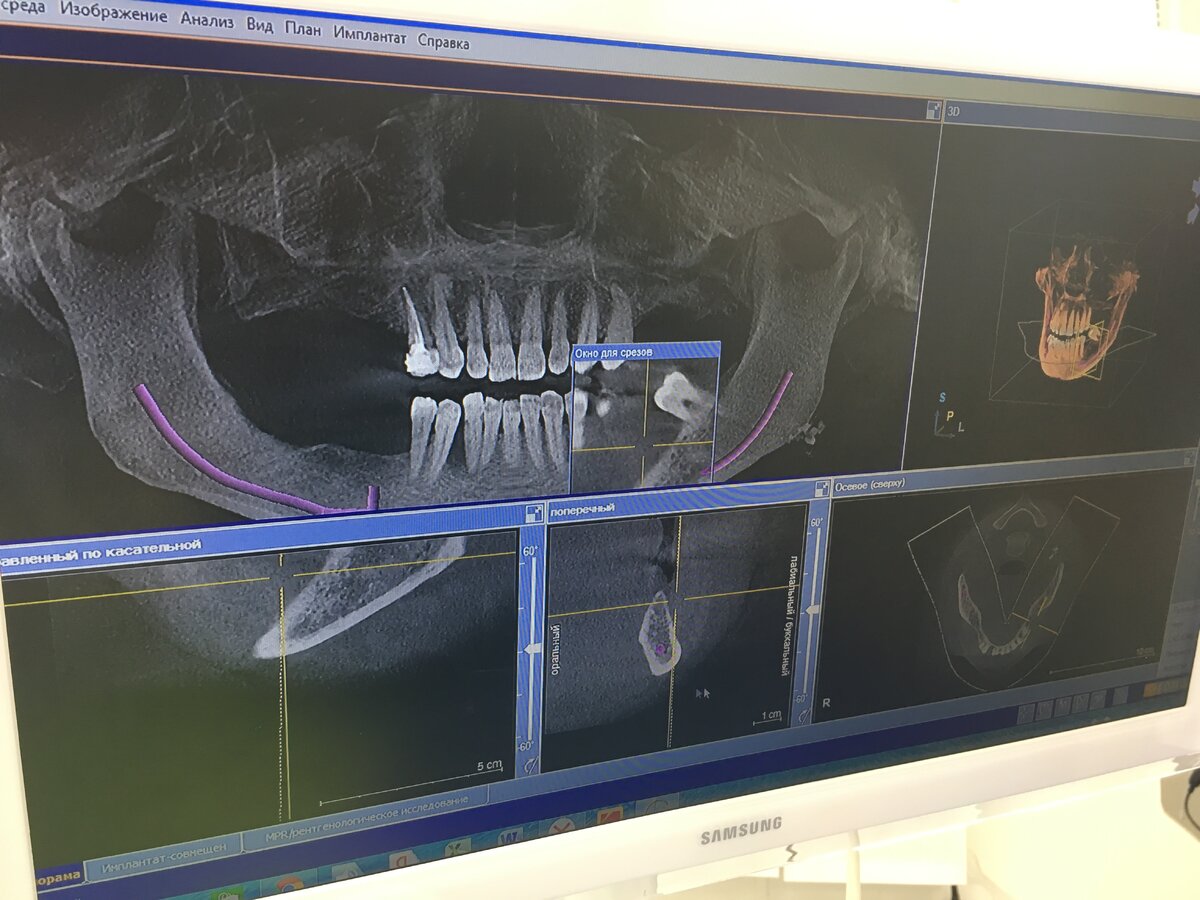

• Пройти консультацию. Как любое важное дело, имплантация начинается с планирования. Первичный осмотр у врача-имплантолога, на которой доктор знакомится с ситуацией и предлагает варианты решений, опираясь на опыт. Изучение компьютерной томографии (КТ), на которой видно буквально всё. Эти первые шаги помогут точно знать, что нужно сделать и сколько это будет стоить.